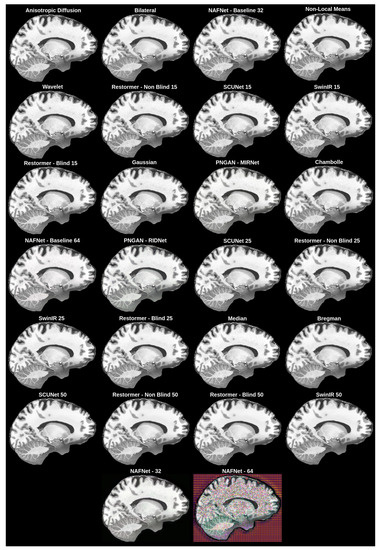

4.3. Results

4.4. Discussion